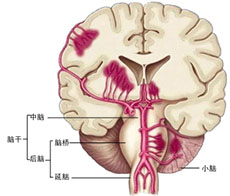

严重颅脑损伤、多发伤、复合伤

疾病介绍:严重颅脑损伤、多发伤、复合伤,多为交通、工矿事故、自然灾害、爆炸、火器伤、坠落、跌倒以及各种锐气、钝器对人体伤害。除正确诊断和及早手术外,加…【详细】